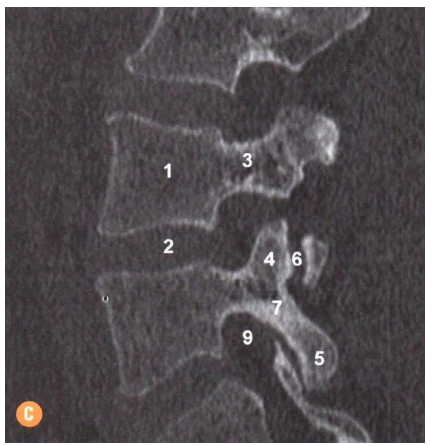

Assinale a alternativa que corresponde a estrutura apontada no número 7 da imagem a seguir: